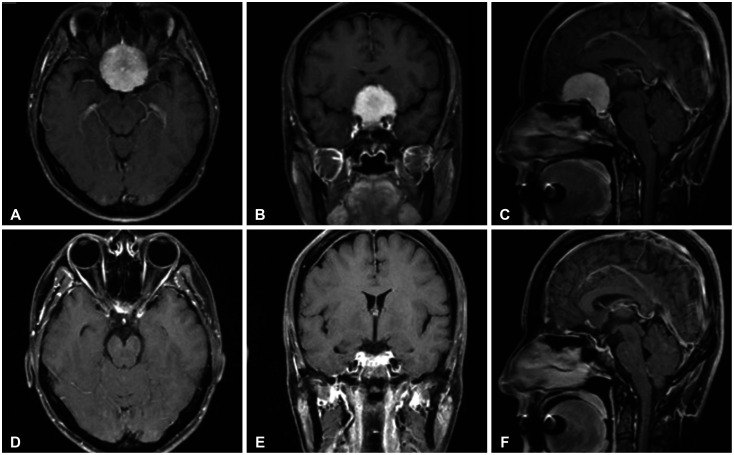

Methods: This study included 33 patients aged 36-83 years who underwent surgery using the SOA for lesions in the inferior frontal lobe, anterior skull base, and parasellar area between 2015 and 2024. There were 25 cases of meningioma, 2 cases of brain abscess, 2 cases of glioma, and one case each of craniopharyngioma, hemangioma, metastasis, and Rathke's cleft cyst. The medical data and follow-up results were retrospectively analyzed.

Results: The mean size of lesion was 3.38±3.05 cm. The mean follow-up period was 48.8 months. Gross total resection was achieved in 25 patients (75.8%). There were no perioperative deaths, cases of cerebrospinal fluid rhinorrhea, or infections. Two cases of morbidity were reported as complications: one case of delayed intracerebral hemorrhage and one case of infarction due to vascular injury. All patients exhibited satisfactory cosmetic results.